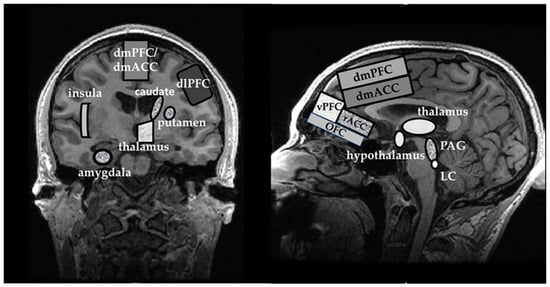

3.2.4. What Does the Evidence from 1H MRS Studies Imply about the ‘Fear Neurocircuitry’?